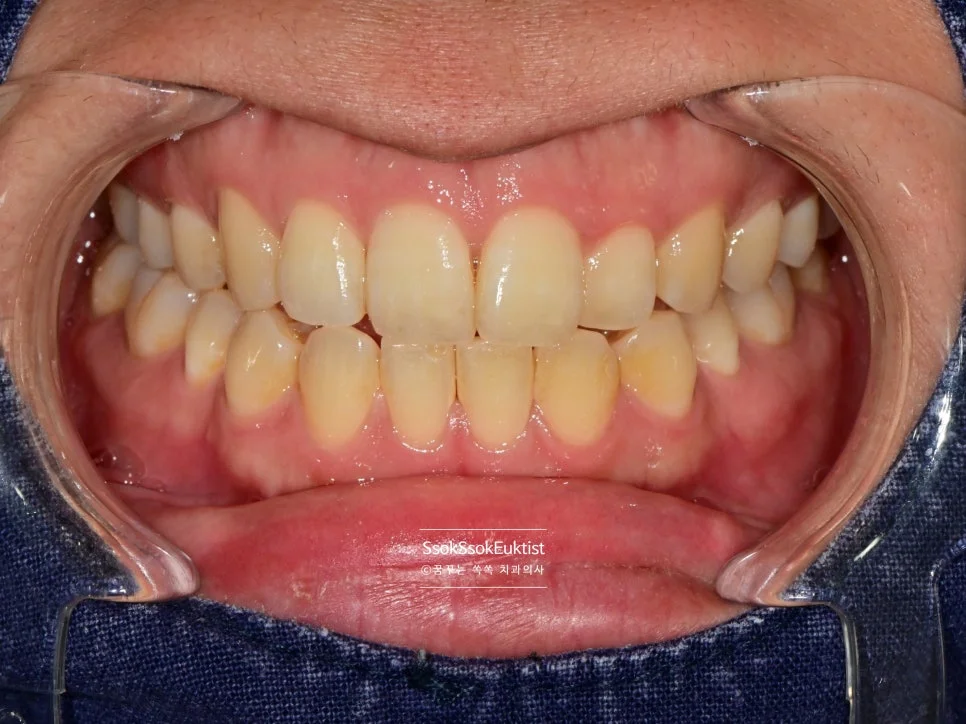

스케일링 전 구강 정면 임상 사진

구강 정면 — 관리가 조금 필요해 보이지만…

이 증례에서도 사진을 보면 구강 내 관리가 조금 필요해 보입니다만,